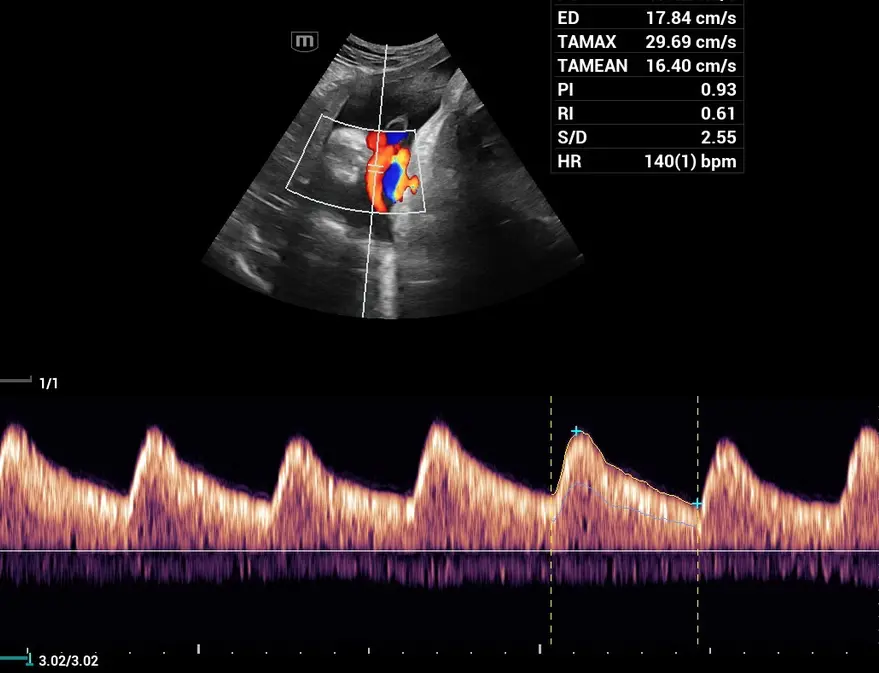

PW Auto Trace

Пулсов доплер с автоматично очертаване на вълната - за измерване на скоростта на кръвния поток.

Измерване в B режим

Измерване в Doppler режим